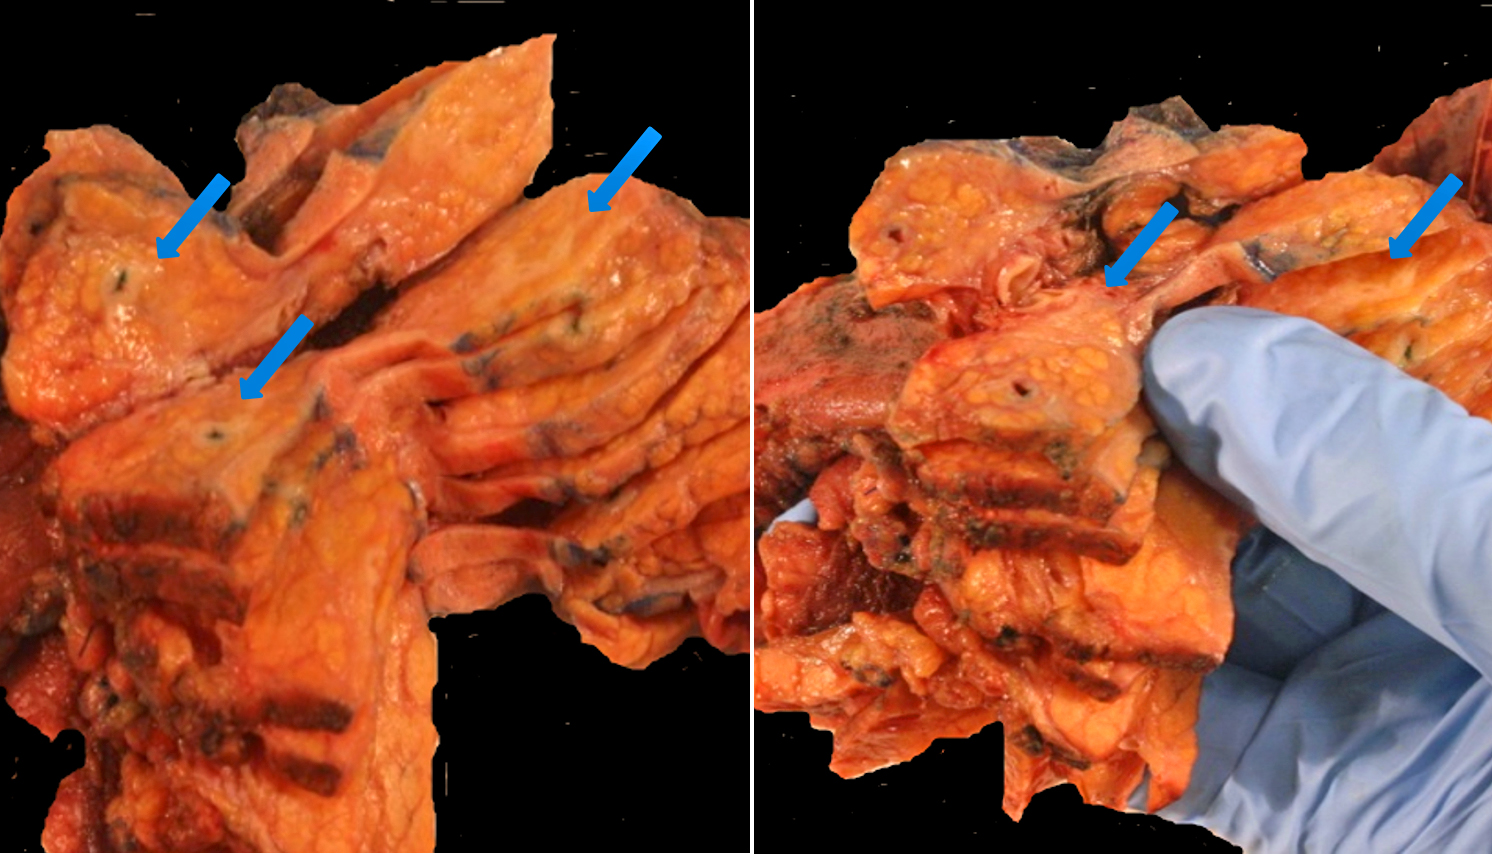

A 65-year-old male presented with abdominal pain and 4-5 pounds weight loss, but no biliary...

Tumor is grossly involving uterine serosa

Myometrium with lymphovascular tumor invasion

Detail of...